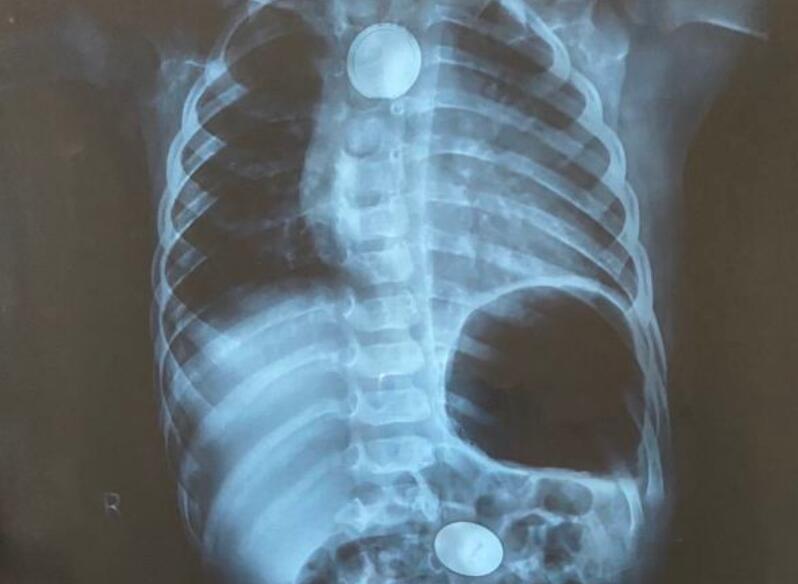

6月15日,1岁4个月的小海(化名)因疑似吞入异物被送往当地医院。小海的妈妈告诉记者,“孩子14号晚饭还吃了粽子,之后就开始出现流口水多,不想吃东西,不舒服。开始,我们怀疑是不是又要长牙了,直到第二天上午没有改善,就带他去了医院。谁想到,医生说可能吞了异物。”然而,更令大家没有想到的是,在当地医院拍片显示小海的体内竟然在两个不同的部位分别有两个圆形金属异物,一个已落入胃中,另一个却卡在了食道。胃镜探查发现食道异物周围有明显发黑和糜烂,异物取出困难,于是建议家长立即将孩子转往南京市儿童医院。

16日凌晨,小海被送往南京市儿童医院,该院耳鼻咽喉科石秋兰主治医师接到电话后立即赶往急诊查看小海的情况,“孩子吞入的异物是圆形金属,结合食道的损伤情况,我们初步判断,食道异物可能是纽扣电池,并且已出现漏液,必须尽快手术取出。”此外,考虑到胃中异物的位置,石秋兰决定与消化科联合手术一次取出两个异物。

手术首先由石秋兰通过硬质食道镜经口插入食道进行探查,发现了食道异物,是一枚圆形的纽扣电池。电池因腐蚀漏液对食道造成碱烧伤,周围组织糜烂、发黑,并与电池包裹粘连在一起。石秋兰小心翼翼地用异物钳夹住电池,动作非常轻柔地将电池剥离组织,一点点往外拉,终于成功取出电池。随后,消化科主任刘志峰在胃镜下将胃中的异物也成功取出,是一枚一角钱硬币。可见,小海是先吞入了一角钱硬币,后于14日晚饭后吞入纽扣电池。最后,因食道创口水肿严重,插胃管非常困难,刘志峰主任在胃镜下顺利为小海置入胃管。